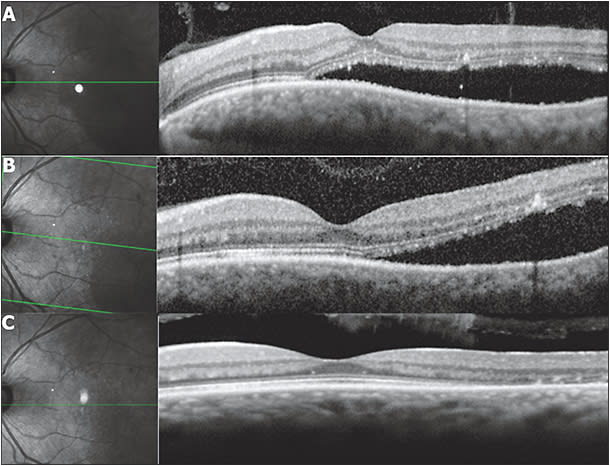

Figure 2. Case of a 54-year-old white man, a known case of chronic CSC for six months, who presented with visual acuity of 20/100 in the right eye and 20/25 in the left eye. He denied previous use of steroids or other medications. The patient was submitted to nondamaging retina laser therapy in the left eye with a 200-μm spot size, 150 mW 100%, 30% energy, 0.25 distance, and landmark optic nerve, with a total of 892 burns. After one month, there was partial resolution of fluid on optical coherence tomography, and VA improved to 20/20. At the two-month follow up, there was a complete resolution of subretinal fluid with further improvement of VA to 20/15